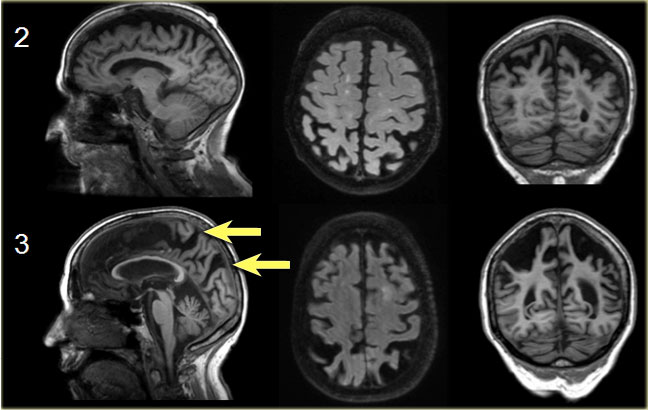

Koedam score for Parietal Atrophy

In addition to medial temporal lobe atrophy, parietal atrophy also has a positive predictive value in the diagnosis of AD.

Atrophy of the precuneus is particularly characteristic of AD (15).

This is particularly the case in young patients with AD (presenile AD), who may have normal MTA-scores.

The Koedam scale rates parietal atrophy - assessed in sagittal, coronal and axial planes.

In these planes, widening of the posterior cingulate and parieto-occipital sulci as well as parietal atrophy (including the precuneus) is rated (Table).

Koedam scale grade 0-1 Koedam scale grade 0-1

Koedam scale grade 0-1

Sagittal T1-, axial FLAIR- and coronal T1-weighted images illustrating the Koedam scale of posterior atrophy.

When different scores are obtained in different orientations, the highest score must be considered (16).

Koedam scale grade 2-3 Koedam scale grade 2-3

Koedam scale grade 2-3

The yellow arrows point to extreme widening of the posterior cingulate en parieto-occipital sulci in a patient with grade 3 posterior atrophy.